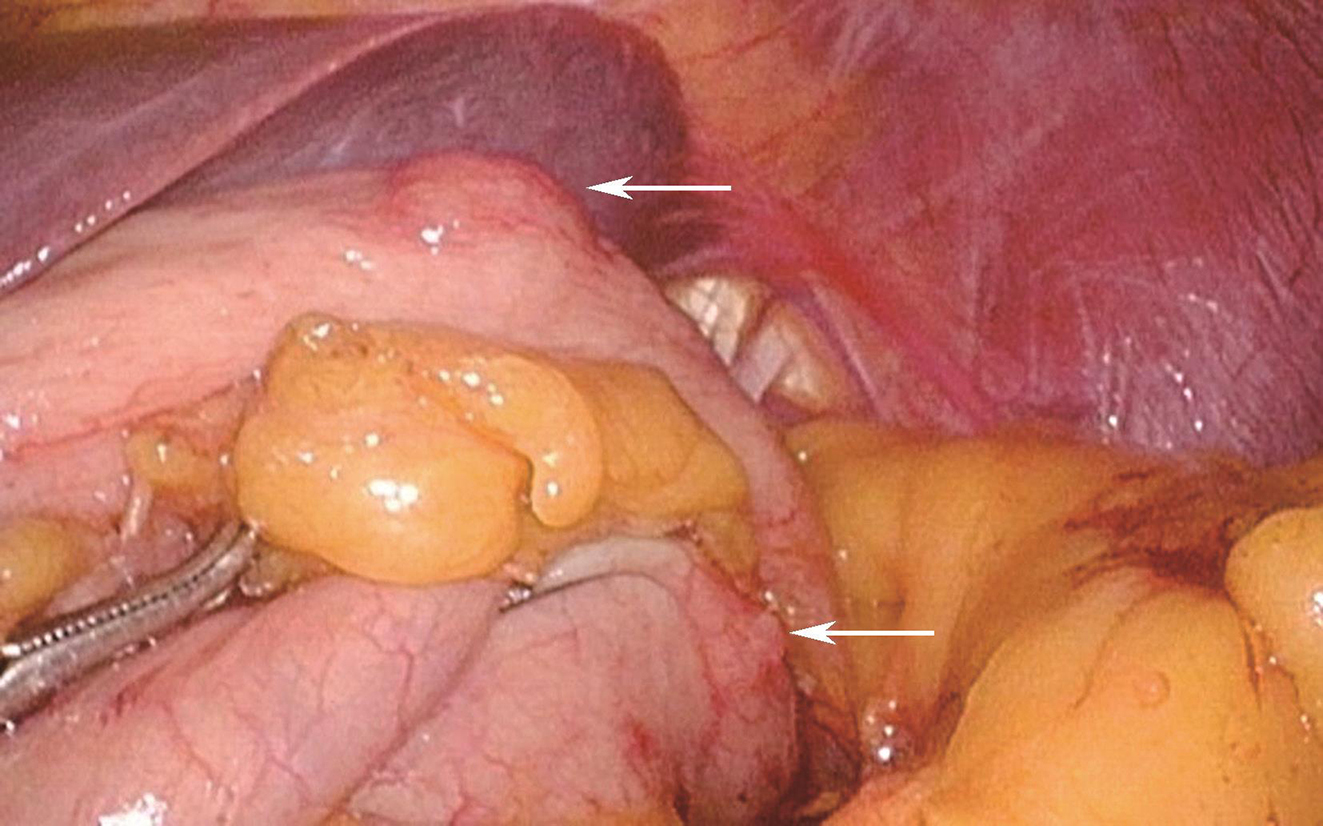

于2017年5月19日行“3D腹腔镜下胃底肿物及部分胃壁楔形切除术”,术中所见:探查腹盆腔未见明显转移结节,肿物位于胃底前壁大弯侧,大小约1.5cm×1cm,游离胃底,于胃底后壁大弯侧见另一肿物,大小约0.5cm(图3),腹腔镜下充分探查其他部位胃壁,未见其他肿物,分别以切割吻合器完整切除两个肿物(图4),术中胃镜下仔细探查胃腔,未见肿物。

图3术中肿物位置

图4切除肿物大体观

A.胃后壁肿物;B.胃前壁肿物